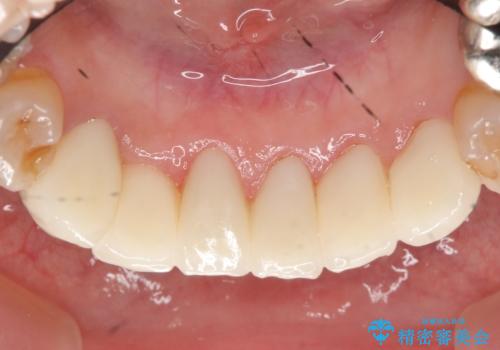

- 上下顎前歯部の見た目が気になるといらっしゃった方の症例です。

上顎は左4番から右4番までの8歯、下顎は左3番から右3番までの6歯、計14歯をオールセラミッククラウンにより補綴しました。

今回用いたオールセラミッククラウンはジルコニアフレームという白い素材の上にセラミックを盛っているため、審美性が非常に高いのが特徴です。

また、ジルコニアは人工ダイヤモンドの材料にも使われているほど高い強度を持っており、そのためオールセラミッククラウンは審美性だけでなく、奥歯やブリッジの補綴も可能とするクラウンです。